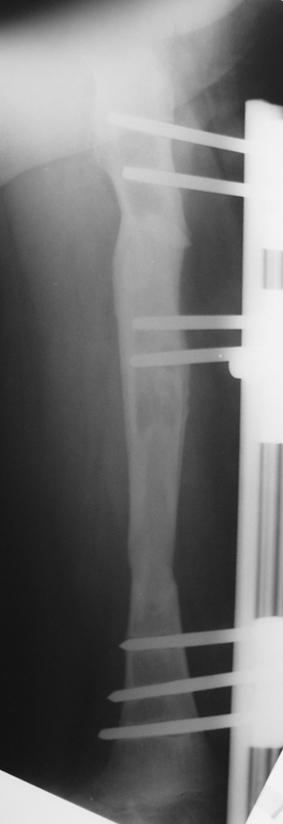

Uygun radikal debridman tüm nekrotik kemik ve yumuşak dokuların çıkartılmasını gerektirir, ve sıklıkla uzuvda instabiliteye neden olur. Kalan kemik ve yumuşak doku defektinin bir şekilde fiksasyonu ve rekonstrüksiyonu gereklidir. İlizarov’un ortaya koyduğu distraksiyon osteogenezi yöntemi, kaynamanın elde edilmesi, deformitenin düzeltilmesi, bacak boy eşitsizliğinin giderilmesi ve segmental defektlerin rekonstrükte edilmesi için başarıyla kullanılmaktadır.

Eksternal fiksatör ile geçen süre (eksternal fiksasyon indeksi), gereken distraksiyon miktarına bağlıdır ve bu süre boyunca bazı komplikasyonlarla karşılaşılabilir. Distraksiyon dönemi sona erdikten sonra, distraksiyon süresinin iki katını aşan konsolidasyon döneminde hastalar eksternal fiksatörü zorlukla tolere edebilirler. Yeterli konsolidasyon sağlanmadan eksternal fiksatör çıkartılırsa ise kırıklar, deformite ve kısalık oluşabilir. Hastanın fiksatör ile birlikte geçirdiği sürenin azaltılması ve böylece hasta konforunun ve aktivite düzeyinin arttırılması için intramedüller çivi üzerinden uzatma yöntemi uygulanmaktadır. Bu yöntemde distraksiyon dönemi sona erdiğinde kemiğin içindeki çivi statik olarak kilitlenmekte ve eksternal fiksatör çıkartılmaktadır. Stabilizasyon intramedüller çivi tarafından sağlandıktan sonra konsolidasyon dönemi gerçekleşmektedir. Bu şekilde hem eksternal fiksatörün uzun süre kalmasından hem de erken çıkartılmasından kaynaklanan komplikasyonların önüne geçilmektedir.

Vaka 3